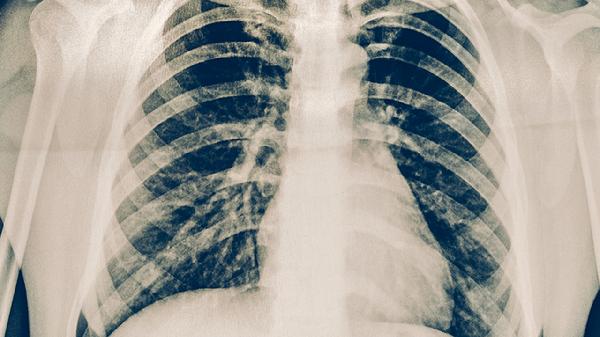

阿莫西林胶囊适用于细菌性肺炎,通过抑制细菌细胞壁合成发挥抗菌作用。糖尿病患者使用需注意可能出现的胃肠道反应,不可自行调整剂量。用药期间要密切监测血糖变化。

盐酸二甲双胍片是2型糖尿病基础用药,可改善胰岛素抵抗。肺炎期间如出现呕吐腹泻需暂停使用,以防乳酸酸中毒。与抗生素联用时要关注肾功能变化。

格列美脲片通过刺激胰岛素分泌降糖,肺炎感染期间可能出现血糖波动,需在医生指导下调整用量。注意防范低血糖风险,特别是夜间和餐前时段。

氨溴索口服溶液能稀释痰液,改善肺炎引起的咳嗽症状。糖尿病患者选择无糖剂型,服用后适当增加水分摄入。注意与降糖药的服用时间间隔。

胰岛素注射液用于控制严重高血糖,肺炎期间可能需要临时强化治疗。要规范注射技术,轮换注射部位,密切监测血糖防止低血糖发生。妥善保存胰岛素避免失效。